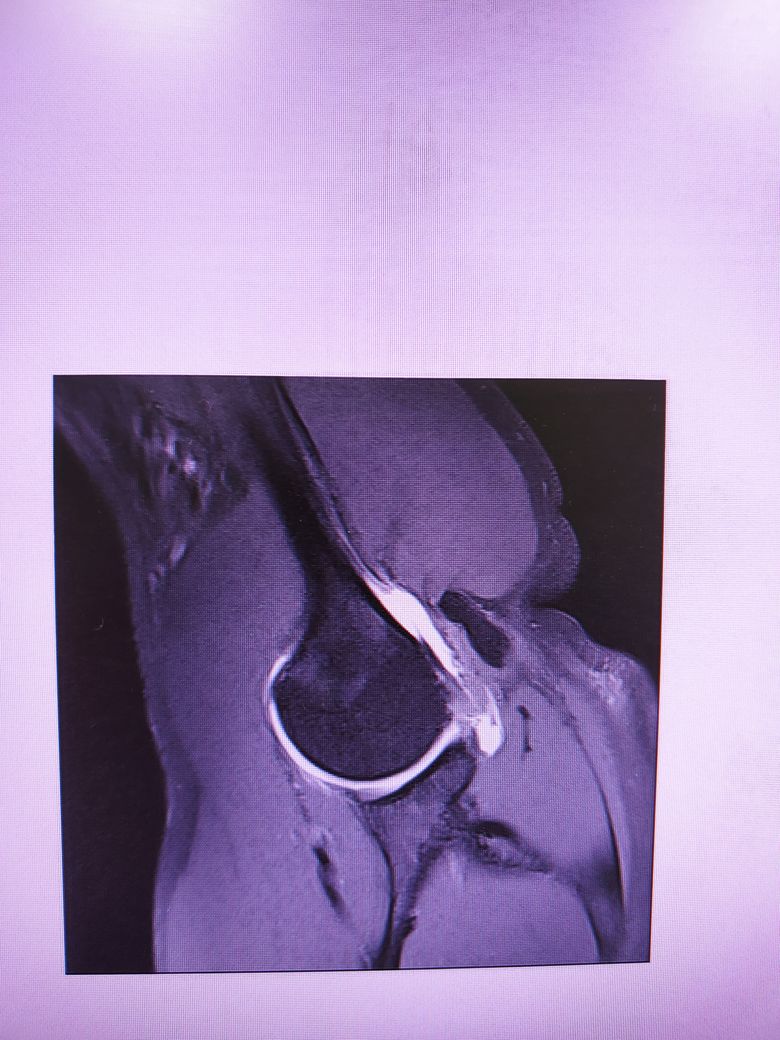

팔이 잡아당겨지는 사고 이후 통증이 지속되어

조영제 투입 후 mri 촬영을 하였습니다.

진단명은 상부관절와순파열(슬랩)이며

헬스와 같은 운동을 계속 하려면 수술이 필요하다 하였습니다.

슬랩이 맞나요? 맞다면 파열 진행 정도는 어느정도인지..